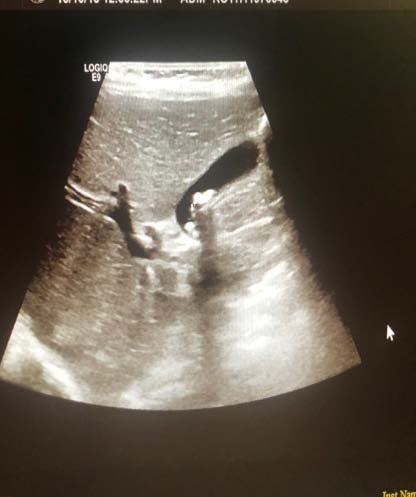

The patient presented 9 months later for reassessment. During this time the mass had increased significantly in size and had become symptomatic and palpable in the left lower quadrant of her abdomen. On repeat CT-scan the mass appeared to have significantly increased in size, measuring 12x 8 x 14 cm. The mass still had a predominantly solid appearance and was strongly associated to the left ovary and likely ovarian in origin. Ovarian cancer markers were repeated and as above stayed within normal limits. Due to the appearance of the lesion and the very rapid growth, a non-benign lesion, possibly of ovarian origin was suspected and an explorative/staging laparotomy was offered to the patient. The patient consented to the procedure. A mid-line laparotomy was performed, and a large retroperitoneal mass was found. This mass was adherent to the left ovary, left ureter, left psoas muscle and external iliac vessels as well as the sigmoid colon. With careful anatomical dissection the mass was resected, and a full staging laparotomy and lymph node sampling of the left pelvic and para-aortic lymphnodes was performed. The specimen comprised of a 527g encapsulated, lobulated portion of tissue, with a histological diagnosis of a well differentiated liposarcoma, sclerosing variant. No areas of dedifferentiated liposarcoma were noted and the margins were clear of tumour. All resected lymph nodes were negative for metastatic disease. The patient had an uneventful post-operative recovery.

? Dedifferentiated liposarcoma ? Myxoid liposarcoma ? Pleomorphic liposarcoma ? Myxoid pleomorphic liposarcomaIn atypical lipomatous tumour/well differentiated liposarcoma adipocytic variant consists out of cells that vary substantially in size as well as cells that have Dedifferentiated liposarcoma can arise as a synchronous lesion in 90% of cases and as metachronous lesion in 10% of cases 6 . These tumours exhibit a wide morphological spectrum and histologically show areas of high grade, poorly differentiated sarcoma resembling high-grade myxofibrosarcoma, fibrosarcoma, malignant solitary fibrous tumour or pleomorphic sarcoma not otherwise specified. Dedifferentiated liposarcomas can be of variable histological grade 5 . Dedifferentiated liposarcomas is an aggressive disease, arising most commonly in the retroperitoneum and is associated with high rates of local and metastatic recurrence and disease specific mortality 7 Use of the term atypical lipomatous tumour is determined by tumour location and resectability. In locations such as the retroperitoneum, it is usually impossible to obtain a wide tumour free surgical margin of more than 2cm, thus local recurrence is common and leads to mortality, seen in the absence of dedifferentiation or metastases The introduction of computed tomography (CT), magnetic resonance imaging (MRI), and ultrasonography have greatly enhanced our capability to make the diagnosis of abdominopelvic neoplasms and determine and direct treatment, as well as observe the progress of the neoplasm and effect of treatment over time. Identification of a retroperitoneal mass at imaging is a challenging task for radiologists, however the presence of fat within a retroperitoneal lesion is helpful in refining the differential diagnosis 9 ? On ultrasound appearance it is hyperechoic and may demonstrate posterior acoustic shadowing . It is easy to recognize fat within a lesion due to its characteristic imaging appearance: